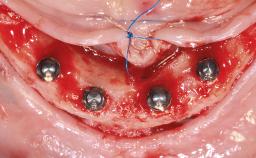

Treatment of the Atrophic Maxilla Using Two Standard Implants and Two Zygomatic Implants Immediately Loaded with a Fixed Restoration

A 65-year-old woman was referred to our clinic by another dentist she had recently visited and who had diagnosed a compromised and complex clinical and anatomical situation. She complained of pain and difficulty when chewing, instability of her maxillary prosthesis, and unsatisfactory esthetics. She had received maxillary implants restored with partial fixed dental prostheses, but no stable clinical solution had been achieved. She expressed a preference for a fixed maxillary rehabilitation.